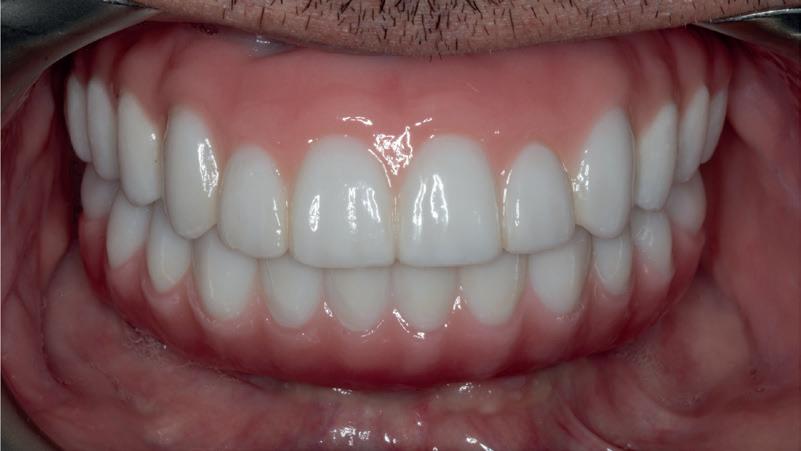

REABILITAREA implanturilor în zona estetică. Acest articol detaliază două cazuri rezolvate prin tehnica extracției parțiale, finalizate fără grefarea compartimentului dintre implant și scut, și monitorizate cinci ani, dovedind stabilitatea volumetrică a țesuturilor moi și dure în timp.

și „punte cu trei unități”, în prezent fiind la egalitate cu majoritatea sistemelor de titan. Deși datele pe termen lung nu au confirmat încă aceste rezultate bune, succesul de până acum este încurajator, astfel încât clinicienii profită de beneficiile clinice ale dioxidului de zirconiu în practica zilnică, introducând implanturile ceramice ca opțiune suplimentară în spectrul de opțiuni alături de cele de titan (fig. 1). Chiar

În plus, aceste proprietăți bioinerte par să aibă și beneficii în ceea ce privește dezvoltarea periimplantitei și calitatea țesuturilor moi. În comparație cu titanul, dioxidul de zirconiu prezintă acumulare de placă și aderență bacteriană mai redusă, precum și o grosime mai mică a biofilmului depus. Și fluxul sanguin circulant către țesuturile moi este mai asemănător cu cel al unui dinte natural în cazul ceramicii față de titan, care oferă flux sanguin redus semnificativ. Se știe că o circulație sanguină mai bună înseamnă țesuturi moi mai sănătoase, care, la rândul lor, prezintă rezultate estetice îmbunătățite. Deși deocamdată lipsesc dovezile pe termen lung pentru implanturile ceramice, sunt disponibile rezultatele inițiale la 3 și 5 ani, iar tendința, susținută de studii preclinice și experiența clinică, este că dioxidul de zirconiu demonstrează același rezultat - iar în unele studii chiar o pierdere osoasă marginală mai redusă față de implanturile de titan. În această perioadă încă nu s-a descris clinic periimplantită.

Trebuie remarcat, totuși, că în cazul implanturilor ceramice, ca și în al celor de titan, cementita, adică inflamația periimplantară cauzată de reziduurile de ciment, poate duce la periimplantită. În plus, la implanturile din dioxid de zirconiu poate apărea supraîncălzirea la înșurubarea implantului în os, iar suprafețele excesiv de aspre sau poroase ale implantului pot cauza defecte osoase periimplantare din cauza termoconductivității reduse a materialului. Deși sunt necesare mai multe dovezi științifice care să demonstreze o tendință mai scăzută spre periimplantită în cazul implanturilor ceramice, argumentul esențial pentru aceste implanturi bazat pe experiența clinică este starea excelentă și aproape constant lipsită de inflamație a țesuturilor moi periimplantare (fig. 3).